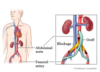

What is an aneurysm?

Localised blood filled balloon-like bulge (weakness) in the wall of a blood vessel (leading to a possible rupture) – Can be the starting point for a thrombus

What is the problem with an aneurysm?

Can lead to a possible rupture